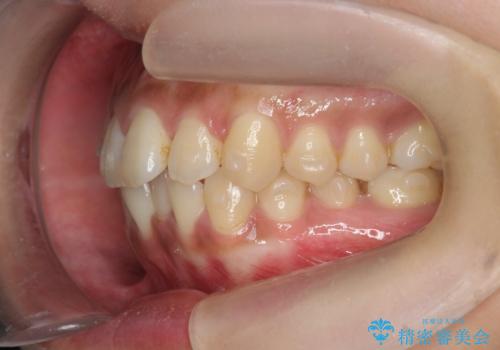

前歯のがたつきをすっきり マウスピース矯正

- 長年気になっていた前歯のがたつきをマウスピース矯正で治したい!と希望され来院されました。

奥歯の噛み合わせには問題がなく、前歯のがたつきの改善のみで十分に審美的な結果が得られるため、ワイヤーではなくマウスピース矯正での治療を計画します。

しっかりと前歯のがたつきは改善し見た目が大きく良くすることができました。